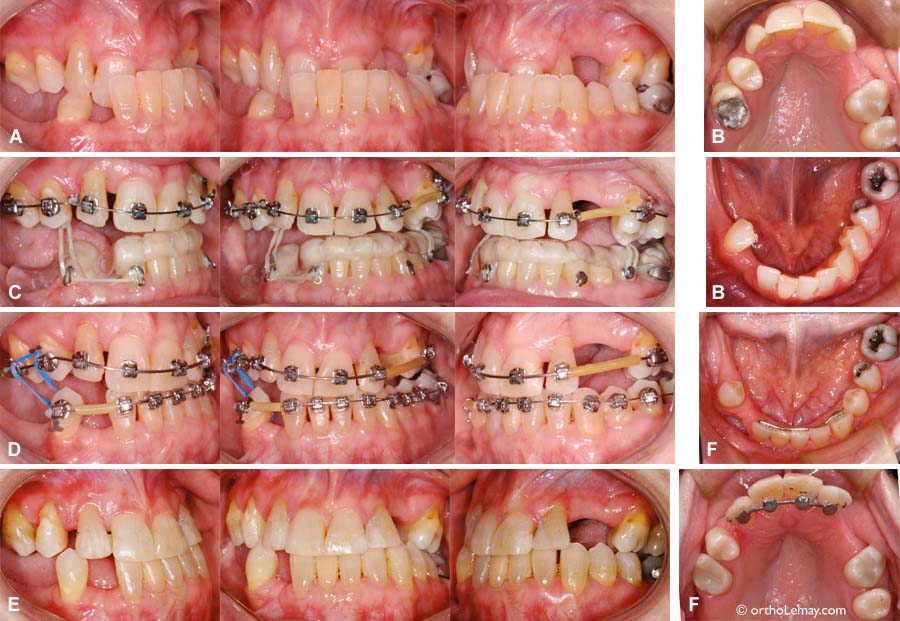

Exemple de traitement de malocclusion classe 1 (1)

Adolescente de 14 ans.

(A) Malocclusion dentaire de type classe 1 (classe I) avec manque d’espace modéré et les canines supérieures non fonctionnelles. L’arcade supérieure est légèrement étroite.

(B) Corrections orthodontiques sans extractions. La forme des arcades a été harmonisée et de l’espace a été créé pour loger les canines supérieures et les rendre fonctionnelles. Les contacts postérieurs verticaux s’ajusteront avec le temps et l’engrenage des dents s’améliorera. (Photos prises 2 semaines après la dépose des appareils correcteurs).

Cas 3 – Déficience maxillaire squelettique transverse et antéro-postérieure

Traitement de compromis en orthodontie pour une classe 3 squelettique adulte.

(A) Importante malocclusion “classe 3” causée un déséquilibre squelettique pour lequel la chirurgie n’était pas une option pour la patiente.

(A et B) Occlusion initiale. Les dents supérieures mordent complètement derrières celles du bas à l’avant ET à l’arrière. Un léger glissement antérieur de la mandibule exacerbe ce décalage.

(C) Mécanique utilisée au début des corrections; une plaque occlusale inférieure servait d’ancrage pour utiliser des élastiques et des appareils multi-bagues pour commencer à “élargir” le haut (expansion).

(D) Par la suite, la plaque inférieure fut retirée et les “broches” furent posées à l’arcade mandibulaire.

(E) Résultat final, la relation entre les dents est fonctionnelle mais constitue un compromis qui est une compensation dento-alvéolaire pour un déséquilibre squelettique important (camouflage orthodontique).

(F) Vue occlusale des arcades à la fin des corrections. Comparez le changement de forme et largeur avec la condition initiale (B).